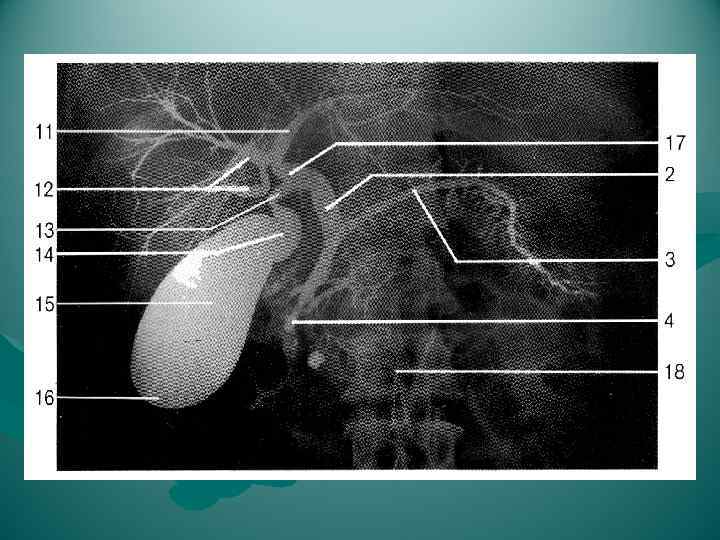

Взаимоотношение поджелудочной железы с двенадцатиперстной кишкой, общим желчным протоком, воротной и нижней полой венами, брюшной аортой и ее ветвями. 1 — v. cava inferior; 2 — aorta abdominalis; 3 — truncus coeliacus; 4 — a. gastrica sinistra; 5 — a. lienalis; 6 — v. lienalis; 7 — v. mesenterica inferior; 8 — a. mesenterica superior; 9 — v. mesenterica superior; 10 — caput pancreatis; 11 — duodenum; 12 — a. gastroduodenalis; 13 — a. hepatica communis; 14 — a. hepatica propria; 15 — ductus choledochus; 16 — a. gastrica dextra; 17 — v. portae; 18 — ductus cysticus; 19 — ductus hepaticus communis.

Взаимоотношение поджелудочной железы с двенадцатиперстной кишкой, общим желчным протоком, воротной и нижней полой венами, брюшной аортой и ее ветвями. 1 — v. cava inferior; 2 — aorta abdominalis; 3 — truncus coeliacus; 4 — a. gastrica sinistra; 5 — a. lienalis; 6 — v. lienalis; 7 — v. mesenterica inferior; 8 — a. mesenterica superior; 9 — v. mesenterica superior; 10 — caput pancreatis; 11 — duodenum; 12 — a. gastroduodenalis; 13 — a. hepatica communis; 14 — a. hepatica propria; 15 — ductus choledochus; 16 — a. gastrica dextra; 17 — v. portae; 18 — ductus cysticus; 19 — ductus hepaticus communis.